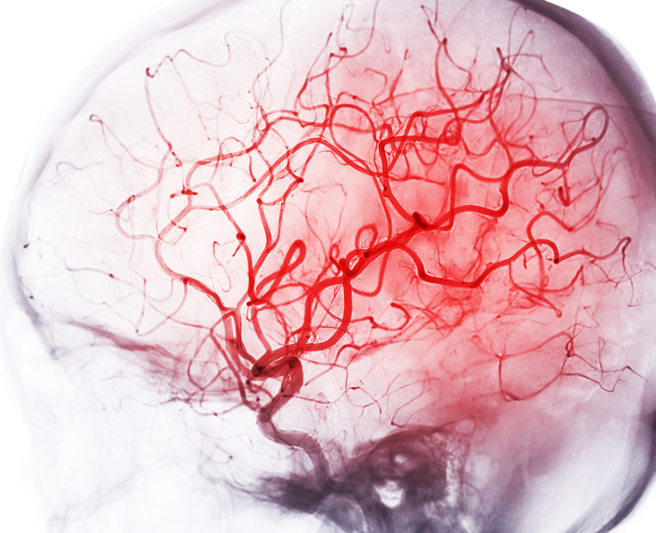

Stroke is a leading global health issue, with ischemic stroke accounting for a majority of cases. Mechanical thrombectomy (MT) has emerged as a transformative treatment for acute ischemic strokes caused by large vessel occlusions (LVOs), significantly improving outcomes. MT involves the physical removal of clots via endovascular techniques, typically within 24 hours of symptom onset. Imaging technologies such as CT angiography (CTA) and computed tomography perfusion (CTP) are crucial in identifying candidates for MT by assessing salvageable brain tissue and occlusion sites.

• Ischemic cascade: Acute LVO interrupts cerebral blood flow, causing irreversible damage to the ischemic core while leaving surrounding penumbral tissue salvageable if blood flow is promptly restored.